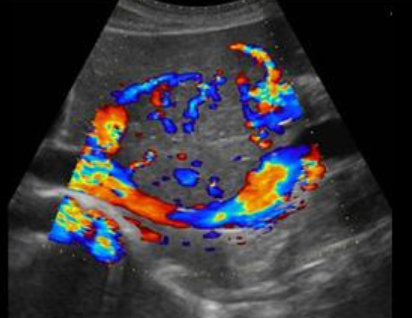

FNH (Focal Nodular hyperplasia) US finding

- isoechoic lesion

- central feeding artery

위에서 보인 초음파소견처럼 FNH는 경계가 명확한 균일한 종괴이며 내부에 섬유성 반흔이 있다. 에코는 저에코를 갖지만 간혹 고에코나 등에코등 다양하게 나타날 수 있으며 피막이 없다. 도플러상 과혈관성을 보이며 정상 간세포조직을 갖는다. 초음파 만으로 간암과 구별할 수 없으므로 혈액검사, CT 와같이 다양한 검사를 통한 진단이 필요하다.